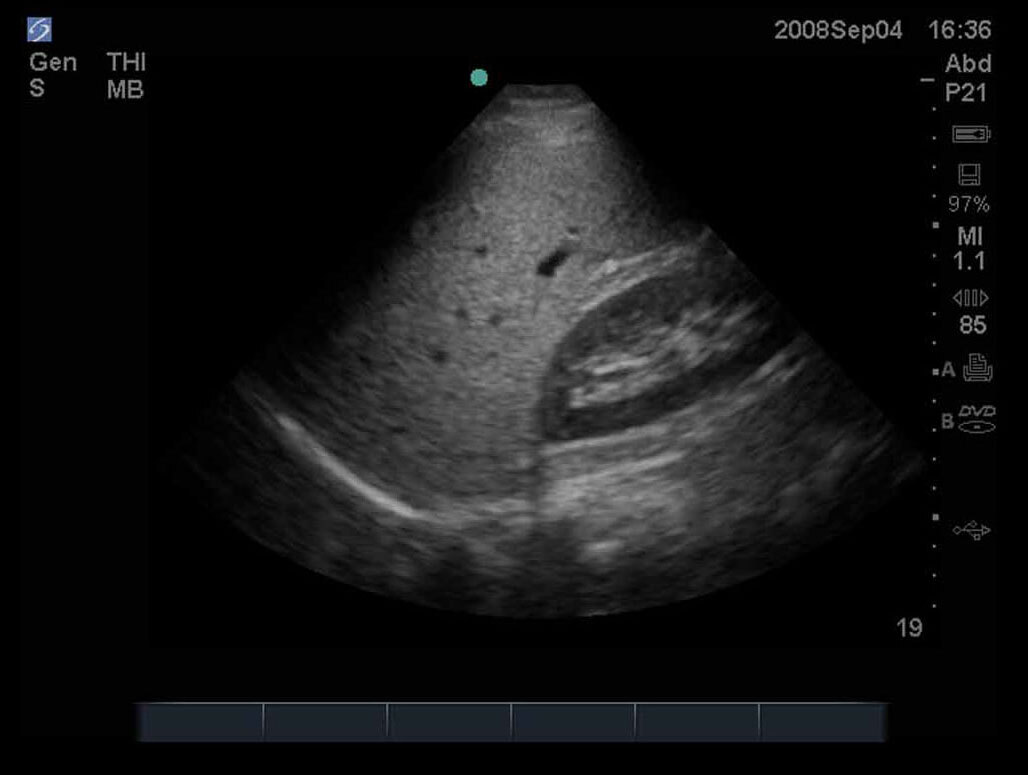

FAST Right Upper Quadrant (RUQ) 3 Image

M-Turbo.